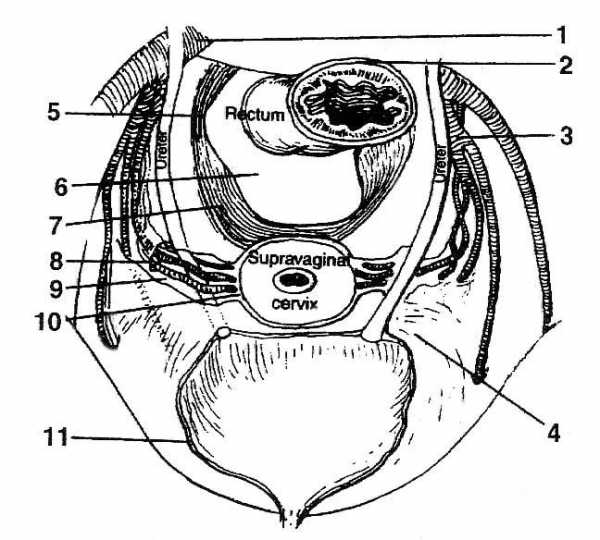

Раздел: Экспозиция интеллекта